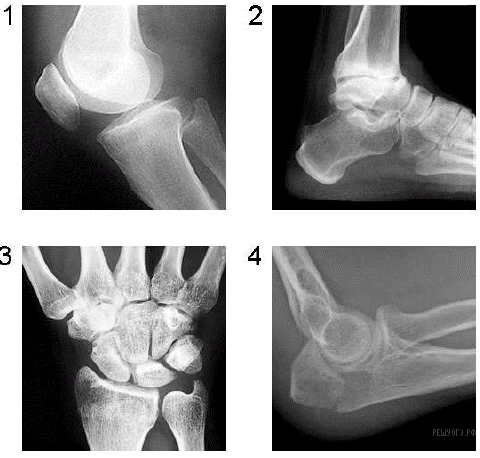

Какой цифрой на рентгенограмме отмечен коленный сустав?

Ответ: